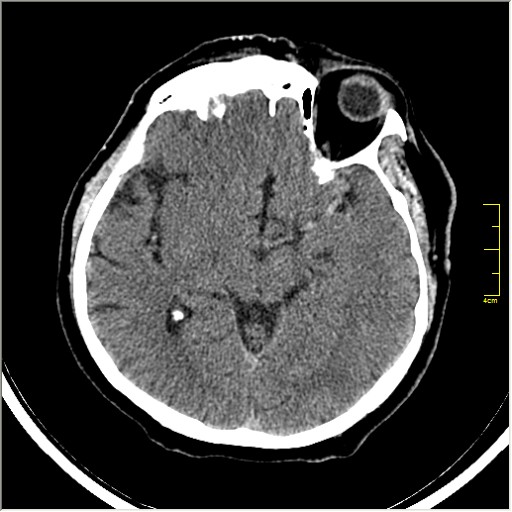

Пациентка Д. 64 года. Поступила с диагнозом ОНМК ???, жалобы на онемение и слабость в левой половине тела.

Ответ: Обратите внимание на правую среднемозговую артерию (MCA); М1 сегмент гиперденсен; сравните с другой стороной.

Этот признак называется [Dense MCA sign]; за счёт наличия тромбоза в её просвете. Этот признак является одним из ранних указующих КТ признаков при ишемическом инфаркте головного мозга. Более подробно об этом вы можете прочитать здесь: http://www.radiologyassistant.nl/en/483910a4b6f14.